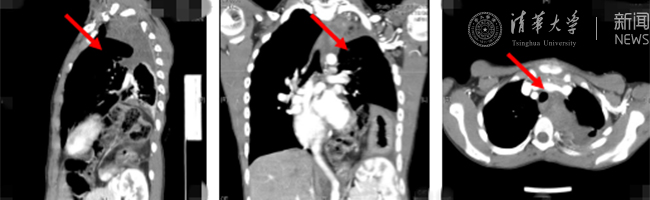

乐动(中国)网8月30日电(通讯员 杨峰)如图中所示,本是正常人心脏、左肺的位置,被发于神经鞘的巨大肿瘤占据,导致一位刚满12岁的男孩胸痛、咳嗽、呼吸困难。近日,北京清华长庚医院神经外科与胸外科联手,由神经外科王贵怀主任主刀,成功为男孩切除胸腔巨大神经鞘肿瘤。

患者胸腔内巨大的肿瘤。

半年前,患者经常会出现胸痛、咳嗽和呼吸困难,在当地医院检查发现左侧胸腔巨大占位,左肺及心脏明显受压。王贵怀大夫接诊,仔细查体了解病情,并反复认真阅片后,认为左侧胸腔巨大肿瘤来自于胸椎椎管内,神经鞘瘤可能性大。该肿瘤体积巨大,占据绝大部分胸腔空间,压迫左肺、纵隔大血管及膈肌。